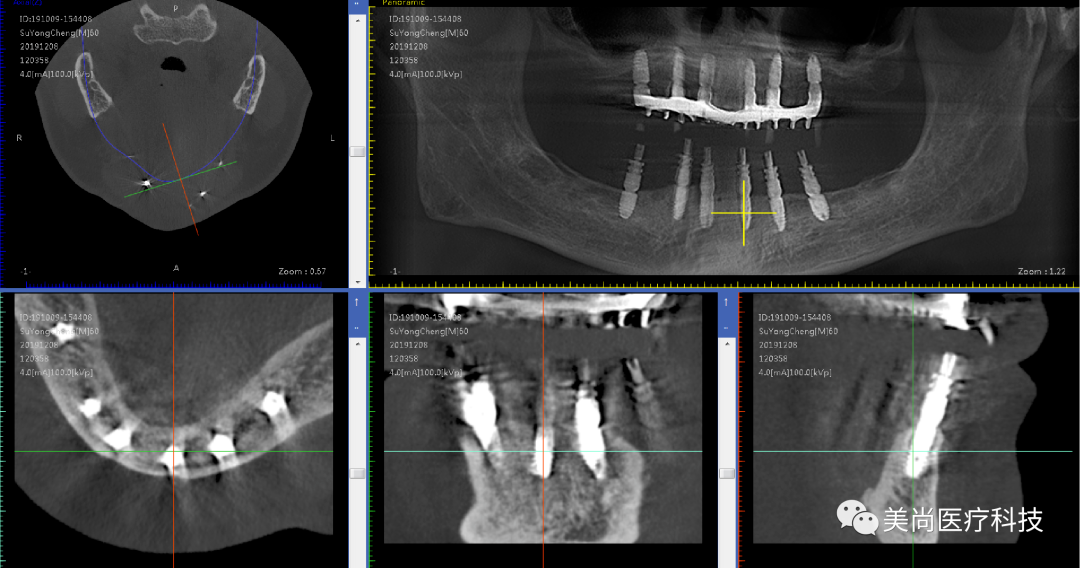

术前X-ray